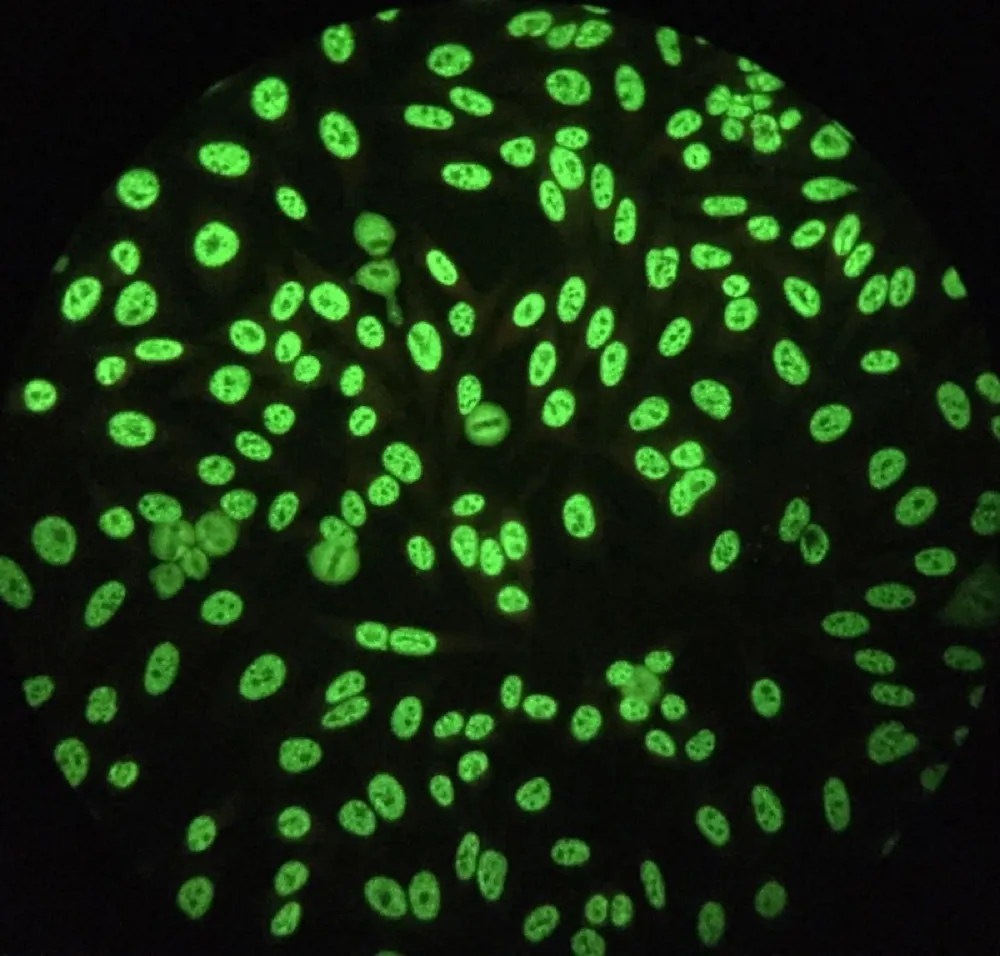

Injúria Renal Aguda (revisão Lancet 2025)

Injúria Renal Aguda (revisão Lancet 2025)